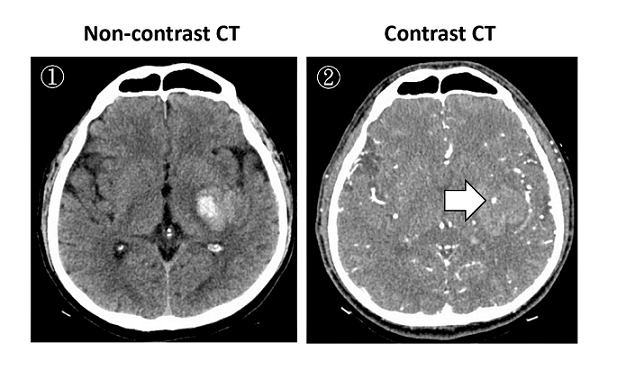

【112-1 醫學(四) 第44題】50歲男性病人突然發生右側肢體無力,無顯影劑之腦部電腦斷層(non-contrast CT)檢查結果如下圖①,經顯影劑造影之腦部電腦斷層如下圖②。於圖②中箭頭所指的小白點,其名稱及意義為何?

這題的關鍵在於辨識腦出血病人做完顯影劑電腦斷層(Contrast CT)後,出血點內出現的小白點。這個小白點代表的是「spot sign」,是活動性出血的徵象,預示著血腫可能會擴大,預後較差。